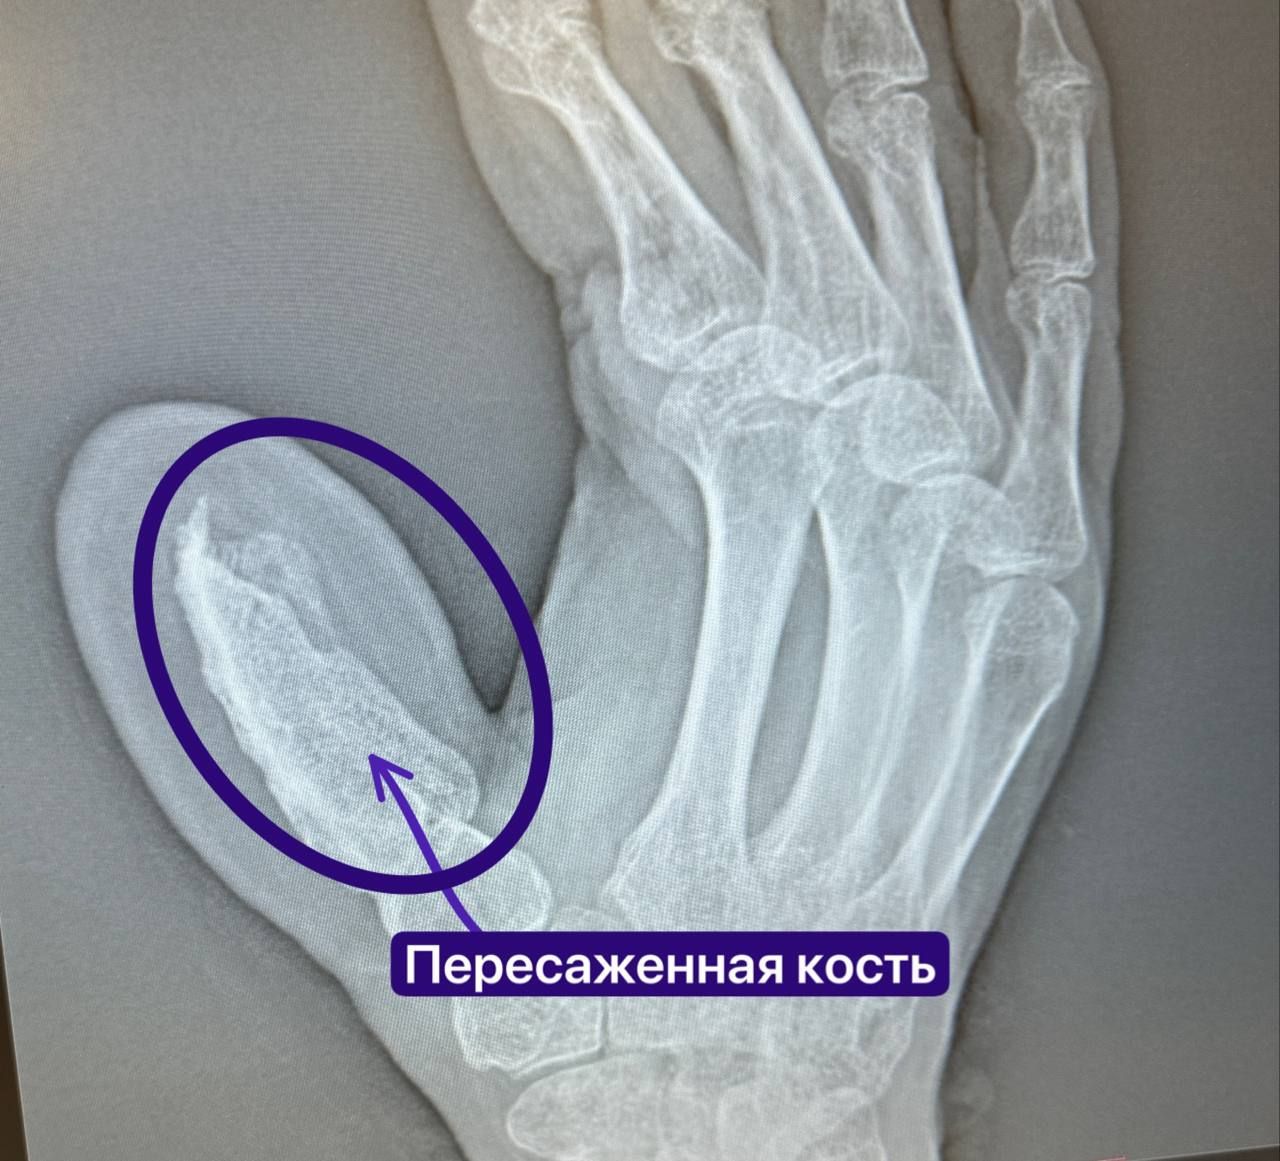

Микрохирурги РКБ вырастили 57-летнему татарстанцу новый палец

01.11.2025, 20:15

Общество